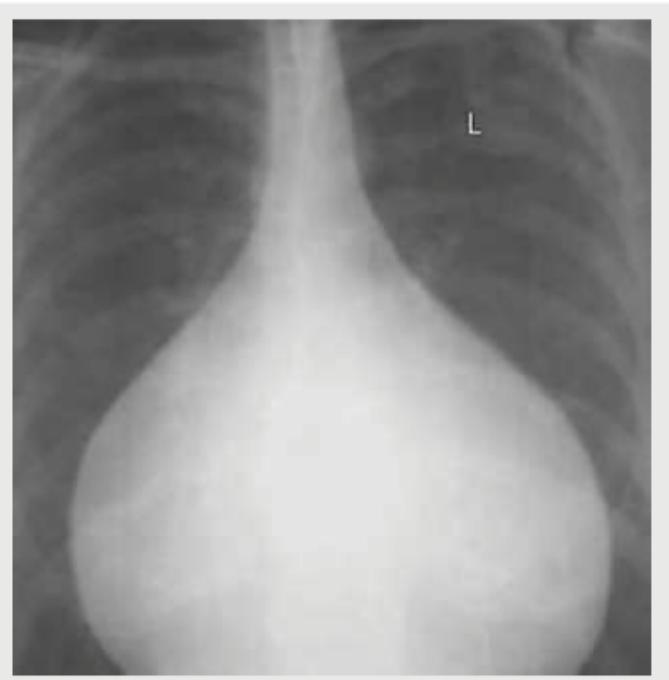

Which is not a finding of the Chest X-ray shown below? (AIIMS May 2017)

Question 2: Which is not a finding of the Chest X-ray shown below? (AIIMS May 2017)

- A. Narrow vascular pedicle (Correct Answer)

- B. Pulmonary venous hypertension

- C. Increased CT ratio

- D. Acute cardiophrenic angle

Explanation: ***Narrow vascular pedicle*** - The image shows a **markedly enlarged cardiac silhouette** with a **"flask-shaped" or "water bottle" heart**, classic for pericardial effusion. In this condition, the vascular pedicle (the mediastinal structures above the heart including the aorta and superior vena cava) is typically **normal to widened** due to venous congestion. - A **narrow vascular pedicle** is characteristically seen in hypovolemia, dehydration, or certain congenital heart diseases with reduced pulmonary blood flow (e.g., tetralogy of Fallot). This finding is **NOT present** in this radiograph. - This is the **most definitively absent finding** among the options listed. *Pulmonary venous hypertension* - The chest X-ray shows prominent pulmonary vascular markings, particularly in the upper lobes, indicative of **cephalization of vessels**, a classic sign of pulmonary venous hypertension. - This occurs due to increased pressure in the pulmonary veins, commonly seen in congestive heart failure or significant pericardial effusion with cardiac tamponade physiology. - This finding **IS present** on the radiograph. *Increased CT ratio* - The **cardiothoracic (CT) ratio** is markedly increased, with the cardiac silhouette clearly exceeding 50% of the thoracic diameter. This indicates **cardiomegaly**, which can result from cardiac chamber enlargement or pericardial effusion. - The extreme enlargement seen here, with the globular "water bottle" configuration, is pathognomonic for large pericardial effusion. - This finding **IS present** on the radiograph. *Acute cardiophrenic angle* - The cardiophrenic angles (the angles formed where the heart border meets the diaphragm laterally) appear **blunted or obtuse** rather than acute (sharp). - While the term "acute cardiophrenic angle" typically refers to the normal sharp angle seen in healthy individuals, the phrasing here is ambiguous. The **angles themselves are present but blunted**, not acute. - However, compared to "narrow vascular pedicle," the blunting of these angles IS a radiographic finding that can be observed, even if abnormal. The vascular pedicle narrowness is completely absent.